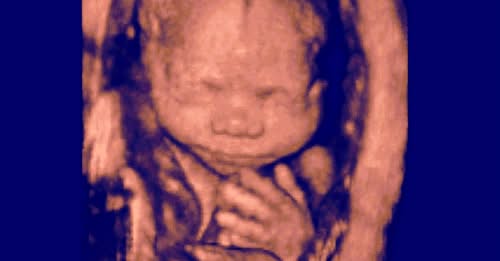

It was a partial-birth abortion. This type of abortion became illegal in the US in 2007 after the Supreme Court case Gonzales v. Carhart upheld a ban against it. I will discuss partial-birth abortions in a minute, but for now, I want to talk about Christina’s experience.

Information on Partial-Birth Abortion

Partial-birth abortion, according to the late abortionist Martin Haskell, who developed the procedure, was created because D&E abortions are difficult to commit on late-term babies…